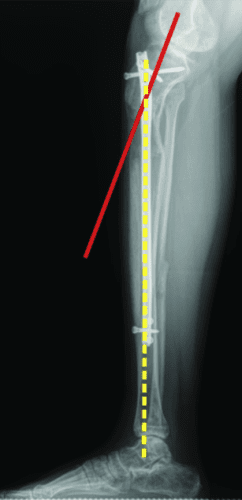

轴向偏斜是胫骨中更常见的问题。胫骨往往会延长成外翻和外翘。为防止这种情况,钉子应插入正确的起点,该起点非常高,并且尽可能靠后,在胫骨的外侧,并在额平面的膝盖中心。如果指甲与截骨术上方的外侧皮层之间有空间,则应在该空间中插入阻挡螺钉。如果指甲与后皮层之间有空间,则在那里插入另一个阻挡螺钉。我设计了 STRYDE 钉子,通过提供第三个近端锁定螺钉(P2.2 只有两个)来抵抗轴向偏差。如果遵循所有这些预防措施,则不会随着延长而出现屈曲或外翻畸形。

敲击(外翻)鞠躬(内翻)

屈曲(procurvatum)

在外部机构胫骨身材延长并出现双侧并发症的患者。他发展了胫骨和 Abu/a 延迟结合,右侧是敲击 {外翻),左侧是弓形 {内翻),两侧是 f1exion {procurvatum}。我们在手术室使用临时外部斧头机对两侧进行了急性矫正,并放置了新的胫骨杆。我们在 Abu/a 延迟结合上放置了逆行杆。